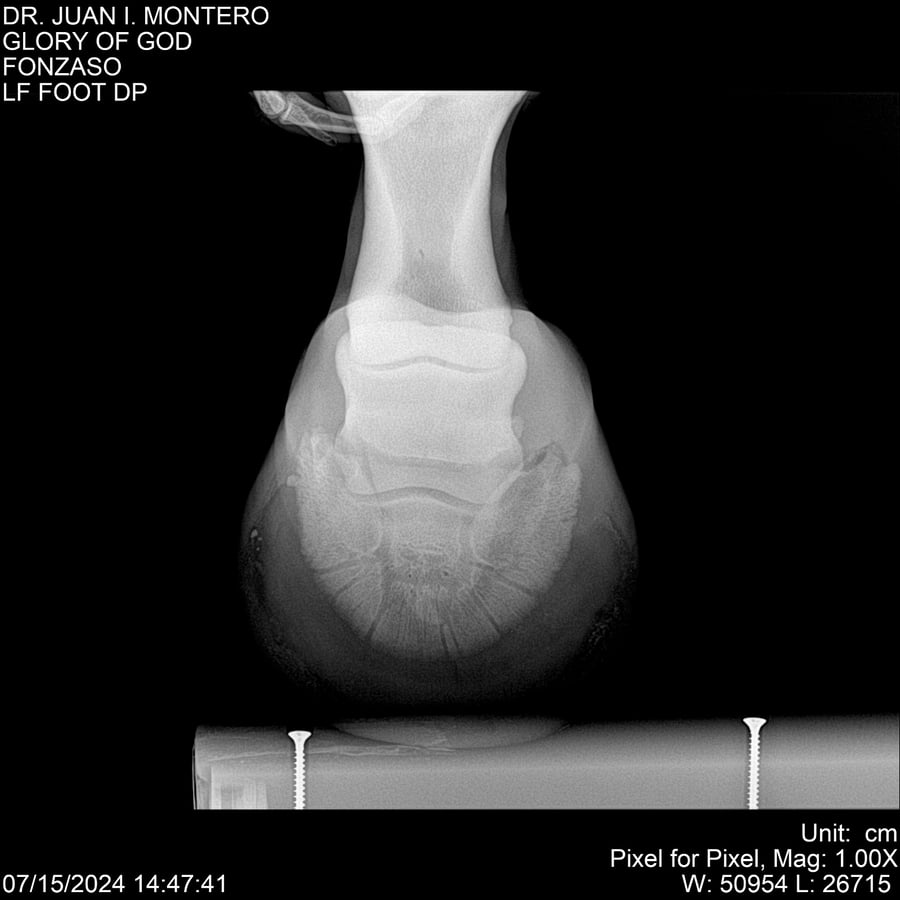

LOTE 10, GLORY OF GOD 🔥 🔥 🔥 Lote Anterior Volver al remate Lote Siguiente Ficha Contacto Montevideo - Ficha del Lote Identificador: #281389 Categoría: Yeguarizos Montevideo - 115 Visualizaciones ClicData Contacto Empresa: Abelenda N. R., Walter Hugo Nombre*: Teléfono* : E-mail* : Mensaje Enviar Registrese gratis Este contenido Exclusivo está disponible sólo para usuarios registrados Ingresar